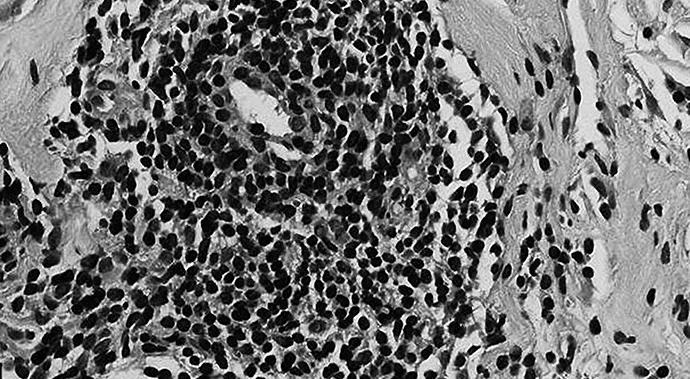

Nonsevere disease covers a wide spectrum of disease manifestations (Figure), which can have a substantial impact on patient quality of life. Management of nonsevere relapses has remained a challenge for which there has been an unmet therapeutic need.

Figure. Two aspects of nonsevere GPA as would have been eligible for treatment in the abatacept trial. (Top) CT demonstrating sinus mucosal disease. (Bottom) CT showing a lung nodule in a patient without respiratory compromise.

The exploration of abatacept in GPA was based on a mechanistic rationale that supported a role for activated CD4 T cells in the pathogenesis of GPA. By containing CTLA4, abatacept blocks the engagement of CD28 with its ligand, thereby inhibiting T cell activation. Based on reasoning that blockage of T cell activation might impact GPA disease pathogenesis, together with the favorable side effect profile seen with its use in rheumatoid arthritis, abatacept was an attractive agent to explore in nonsevere GPA.